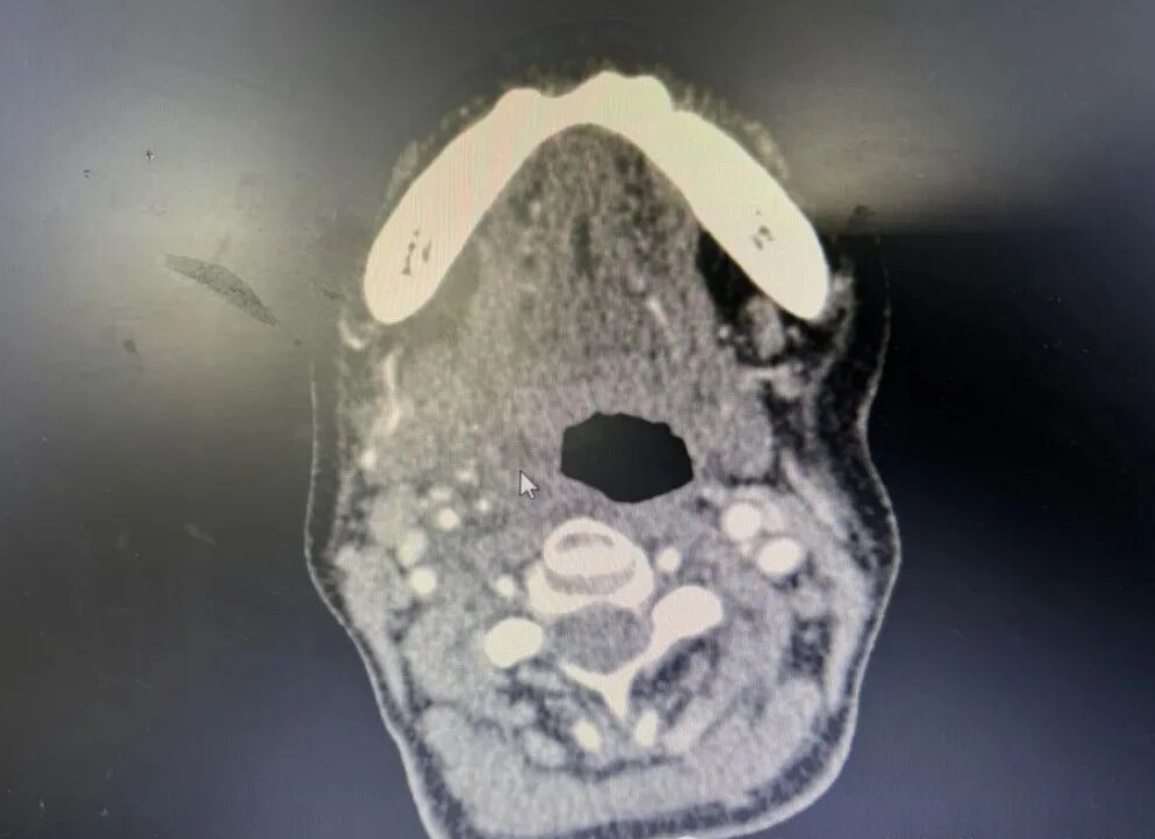

3、影像学检查:喉部CT或磁共振(MRI)辅助诊断。

(▲扁桃体周围脓肿CT显示图)